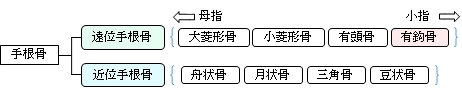

・「日本人体解剖学 (上巻) 「楔状で、近位側、遠位側および外側には関節面を有し、掌側面には先端のやや外側に曲がった突起がある。これを有鈎骨鈎という。 」 また、「船戸和弥のホームページ」では以下のようになっている。 「有鈎骨は第4、5中手骨に対する不正な鞍状の関節面を底として上方に尖る三角形である。掌側面の内側端から掌側に有鈎骨鈎が突出する。内上面は三個角骨にする鞍状の関節面で占められる。」 そして、以下は「Wikipedia」からの抜粋文となる。 The hamate bone has six surfaces:

以下は上記の「Wikipedia」をまとめたものになる。